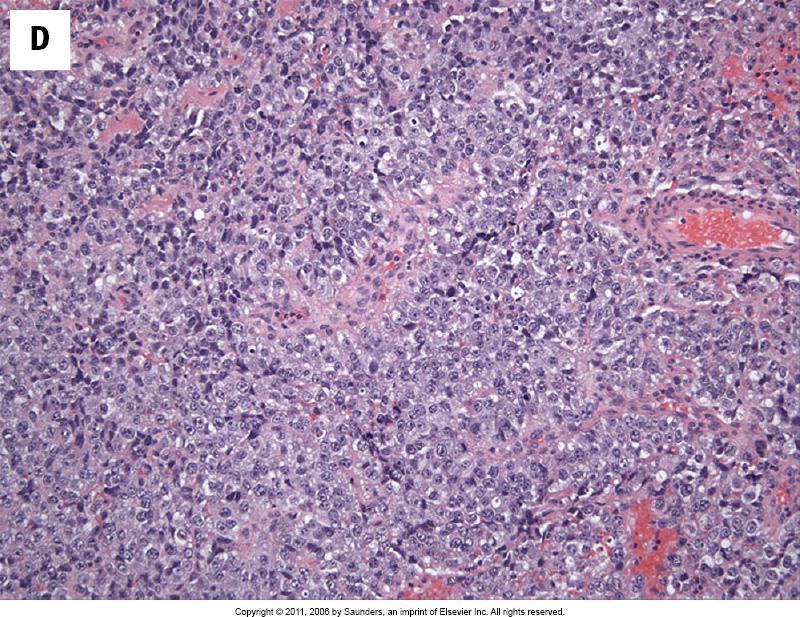

A 65 year old female with bilateral breast lesions. A biopsy of one shows single file cords of tumour cells with intracytoplasmic spaces.

5-14% of breast carcinomas High incidence of multifocal and bilateral disease Tumour cells may show mucin filled vacuoles E-cadherin negative

E-cadherin